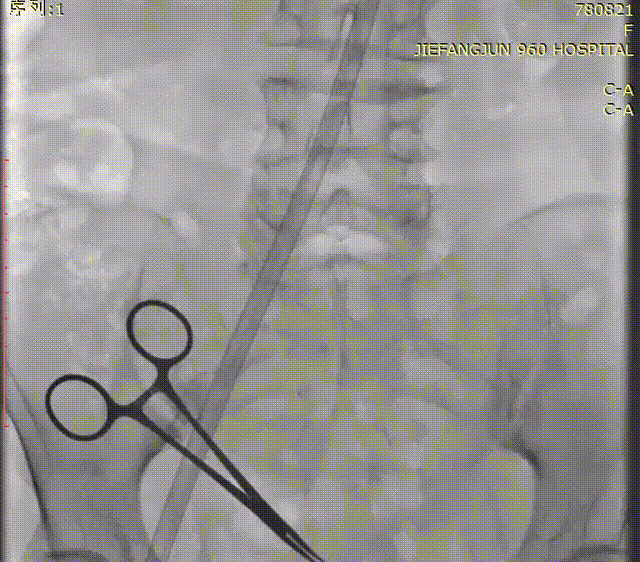

术中,经左侧颈静脉置入临时起搏器,右侧股动脉置入22F大鞘,猪尾导管主动脉根部造影。

入路检查

导丝过髂动脉